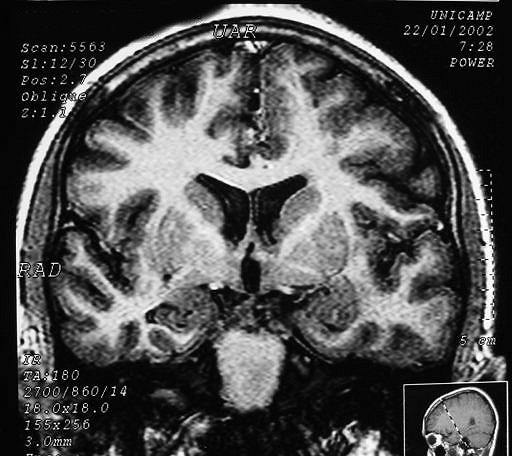

Полимикрогирия.

Приложения:

1.poli_.slayd218.jpg2._poli.slayd219.jpg